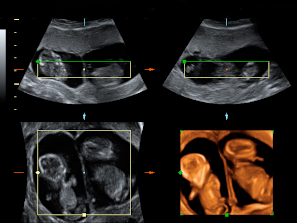

Ecografía Embarazo 4D Semana 12 - ANOMALIAS CROMOSÓMICAS